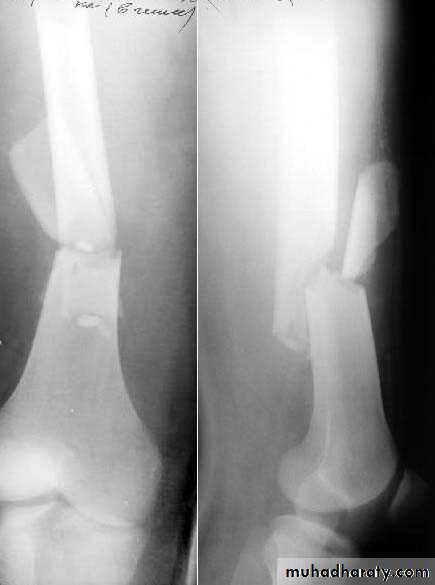

41Physeal injuries

10% of fractures in children

Salter - Harris classification:

1: separation of the epiphysis usually thru the calcified zone

2: separation of epiphysis & triangular piece of metaphysis

Wahby Ghalib

42

3: intra-articular # thru epiphysis then thru physis

4: intra-articular # thru epiphysis, physis, & metaphysis5: crushing of physis arrested growth

44# may not be visible initially

Types 1 & 2 : good Px except around the kneeTypes 3 & 4: need perfect reduction & f/u for re-displacement